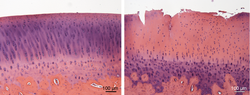

Publication of first results in the Journal of “Disease Models & Mechanisms”: Fetal articular cartilage regeneration versus adult fibrocartilaginous repair: secretome proteomics unravels molecular mechanisms in an ovine model.